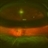

- Fundus photograph of a 76 year old female with neovascular AMD who developed a subfoveal subretinal hemorrhage in the left eye. This photograph is one day postop after 23g vitrectomy, subretinal rt-PA 50ug/0.1cc and C3F8 gas. Note the subretinal hemorrhage and fluid displaced inferiorly. No open retinal break was present.